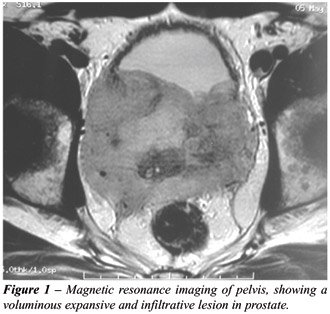

An ultrasonography of the urinary tract showed a 286-gram prostate with moderate bilateral uretero-hydronephrosis. Nuclear resonance imaging was normal in thorax, but the abdominal and pelvic scan evidenced a voluminous expansive and infiltrative lesion exclusive of the prostate, with intense impregnation, measuring 10 x 8 cm (Figure-1), bilateral uretero-hydronephrosis, and absence of lymph nodal involvement. Bone scintigraphy was negative for secondary lesions. Patient evolved to anuria, and subsequently underwent bilateral nephrostomy.